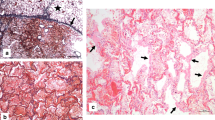

A full autopsy has been performed. Examining the lungs, we found hyperaemic areas of more dense consistency with a particular focus on the centrilobular regions of both lungs and some subpleural hemorrhages (Fig. 1a–d). Minimal pleural effusions (right side: 50 ml, left side: 50 ml) and an intra-alveolar lung oedema accompanied the observed inflammatory processes (Fig. 2d, e). The latter resulted in a lung weight of 1500 g in total (right lung lobe: 855 g, left lung lobe: 645 g). Detailed histologic examination revealed inflammatory changes with a focus on the central areas of both lungs. More precisely, lymphocytic cell infiltration predominantly consisting of CD8 positive cells was found within the interstitial lung areas (Fig. 2e). Local aggregation of CD8 positive cells within the alveoli was found. Disseminated spots of activated type II pneumocytes were observed, and hyaline membranes and the presence of microthrombi within the lungs accompany the reported findings (Fig. 2a, c). Also, hemorrhagic alveolar infiltration was found (Fig. 2b), and mediastinal lymph nodes showed reactive hyperplasia. Concurring inflammatory changes in the lungs, morphological signs of systemic inflammation were found in terms of “septic spleen” and lipid depletion of the adrenal glands.

Microscopic findings of the histologic examination. The lungs of the deceased showed signs of diffuse alveolar damage with hyaline membranes (a), hemorrhagic interstitial and alveolar infiltration (b), the presence of microthrombi (c), and an intra-alveolar oedema (d) (H.&E.). Interstitial accumulation of CD8 positive cells (anti-CD8 antibody) was found in the central areas of both lungs (e). Perivascular astrogliosis (anti-glial fibrillary acidic protein antibody) and mild-to-moderate activation of microglia, with occasional microglial nodules in the frontal cortex (anti-HLA-DR antibody) (f–g). Picture specific scale bars are shown